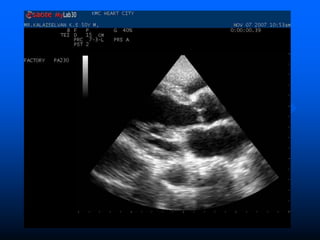

 Trans Thoracic Echocardiograpy (TTE)

– rapid, non-invasive – excellent specificity (98%) but

poor sensitivity

– obesity, chronic obstructive pulmonary disease and

chest wall deformities

 Transesophageal Echo (TOE)

– more invasive, sensitivity up to 95%, useful for

prosthetic valves and to evaluate myocardial

invasion

– Negative predictive valve of 92%